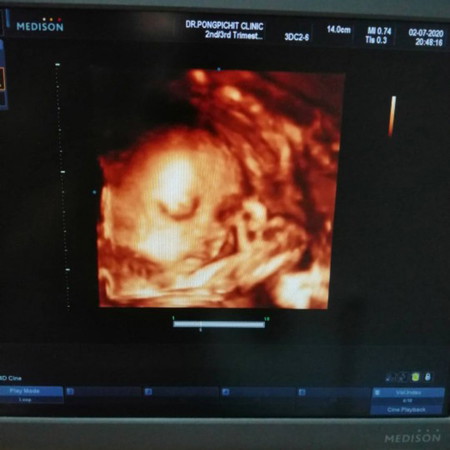

รกเกาะต่ำ (Placenta Previa) คือ ภาวะที่รกปิดขวางหรือคลุมปากมดลูกเพียงบางส่วนหรือปกคลุมทั้งหมด ซึ่งปกติรกจะอยู่ด้านบนของมดลูกและห่างจากปากมดลูก เมื่อถึงเวลาคลอด ปากมดลูกจะเปิดขยายออก ทำให้เส้นเลือดที่เชื่อมต่อระหว่างรกและมดลูกฉีดขาด มีเลือดออกมากทั้งก่อนหรือในขณะคลอด เกิดความเสี่ยงต่อทั้งมารดาและทารกในครรภ์ และอาจทำให้เกิดภาวะคลอดก่อนกำหนดได้ แพทย์จึงนิยมให้หญิงตั้งครรภ์ที่มีภาวะรกเกาะต่ำทำการผ่าคลอด (Caesarean Section)